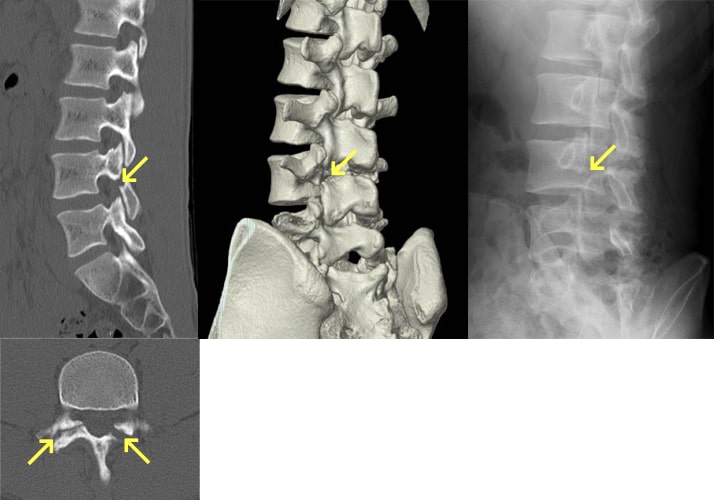

脊椎分離症とすべり症

疲労骨折などにより椎骨が椎弓の関節突起間部で分離したものを脊椎分離症といい、さらに分離した椎体が前方へ転位したものを脊椎すべり症といいます。日本人男性の約8%にみられ、成長期のスポーツ選手の腰痛の原因の30~40%を占めます。症状は腰部から臀部、大腿後面の痛み、背部・分離部の圧痛・叩打痛、神経性間欠跛行などです。治療法としては保存療法と手術療法がありますが、慢性期で痛みが強くない限りは手術は行わず保存療法となります。保存療法は、コルセットや体幹ギプスなどによる固定や運動の制限を急性期には行い、慢性期では薬物療法・分離部のブロック注射などの対症療法に加え、脊椎の負担のかからない動作や姿勢の指導、体幹筋のトレーニングを始めとした理学療法を行います。